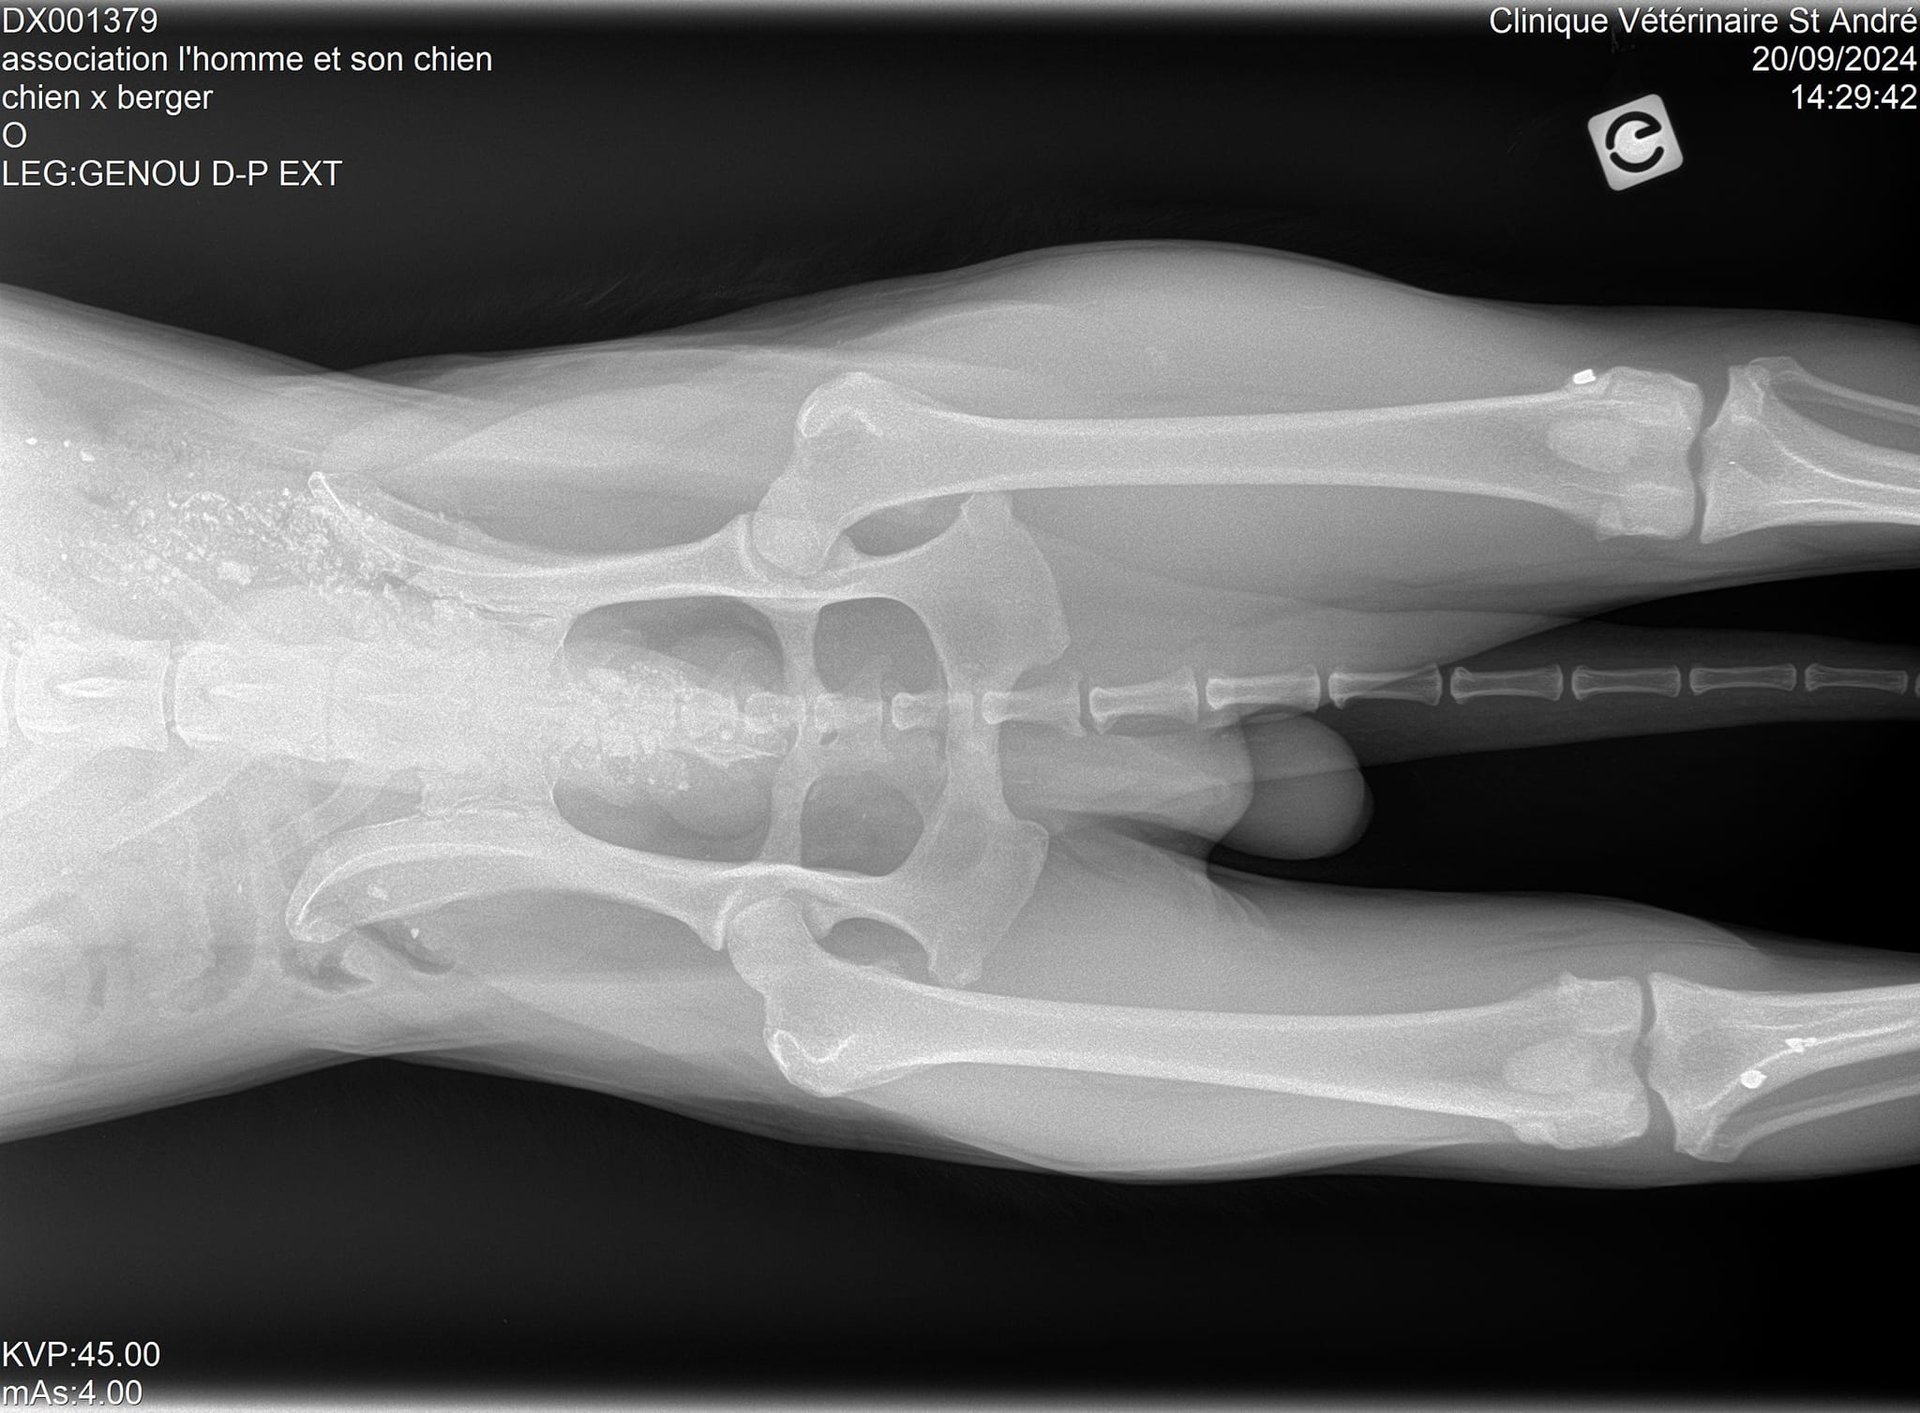

Sa patte avant gauche, criblée de balles, est détruite et, malgré ça, il est obligé de s'en servir car il ne pose pas toujours sa patte arrière droite…

Vous allez halluciner en voyant ses radios !